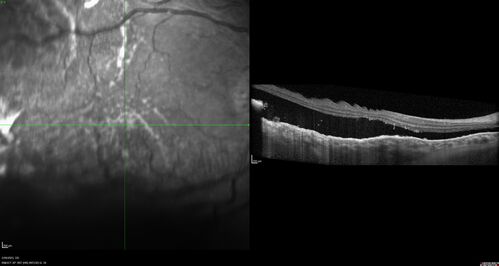

Choroidal Metastatic Breast Cancer with Exudative Detachment

58 year old female presented with 20/200 vision. Had 10 sessions of radiation and tumor shrank. The exudative detachment took almost a year to resolve. The vision improved to 20/40.